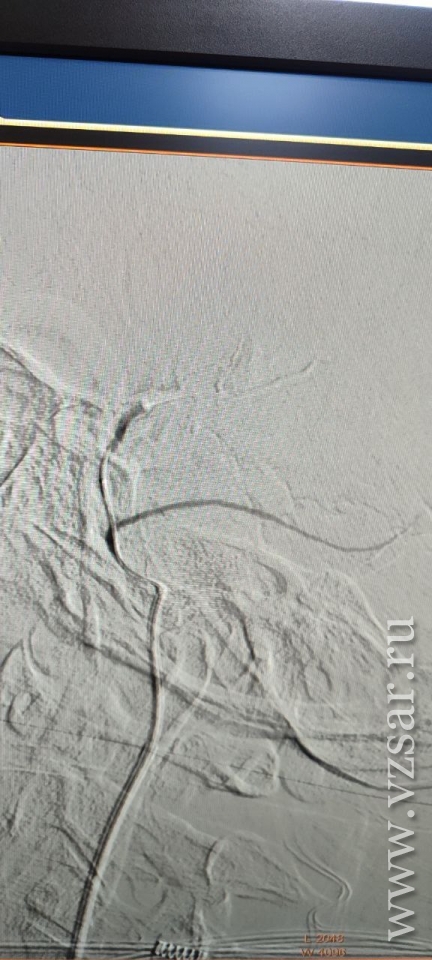

Суть новой эндоваскулярной методики заключается в прицельной внутрисосудистой закупорке этой артерии, что прекращает питание капсулы гематомы и способствует ее постепенному рассасыванию, не влияя на кровоснабжение головного мозга.

Медики успешно выполнила эндоваскулярную эмболизацию средней оболочечной артерии слева микрочастицами. Уже через 4 суток исследование показало значительное уменьшение гематомы - на 20%, а смещение мозга уменьшилось вдвое.